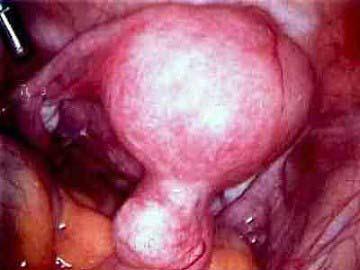

这两图描绘的是浆膜下子宫肌瘤,那么浆膜下子宫肌瘤常见的症状是 ( )A、下腹包块B、腰痛C、痛经D、贫血E、月经过多

问题 这两图描绘的是浆膜下子宫肌瘤,那么浆膜下子宫肌瘤常见的症状是 ( )

选项 A、下腹包块 B、腰痛 C、痛经 D、贫血 E、月经过多

答案 A